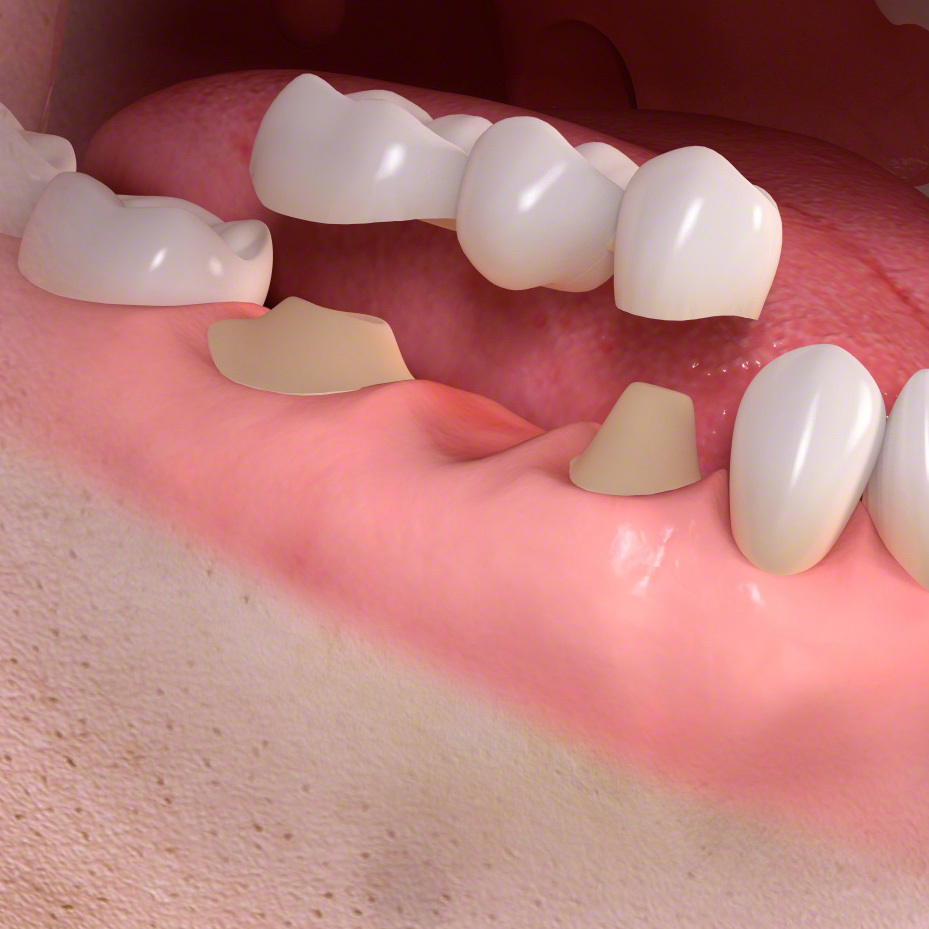

歯の欠損

歯を再生する時、インプラントは前後の歯に固定源を求めない唯一の治療法になります。自費治療になります。

ブリッジは少数の歯を失った時に行う治療法です。

前後の土台になる歯が平行に生えている場合のみ可能な治療法です。